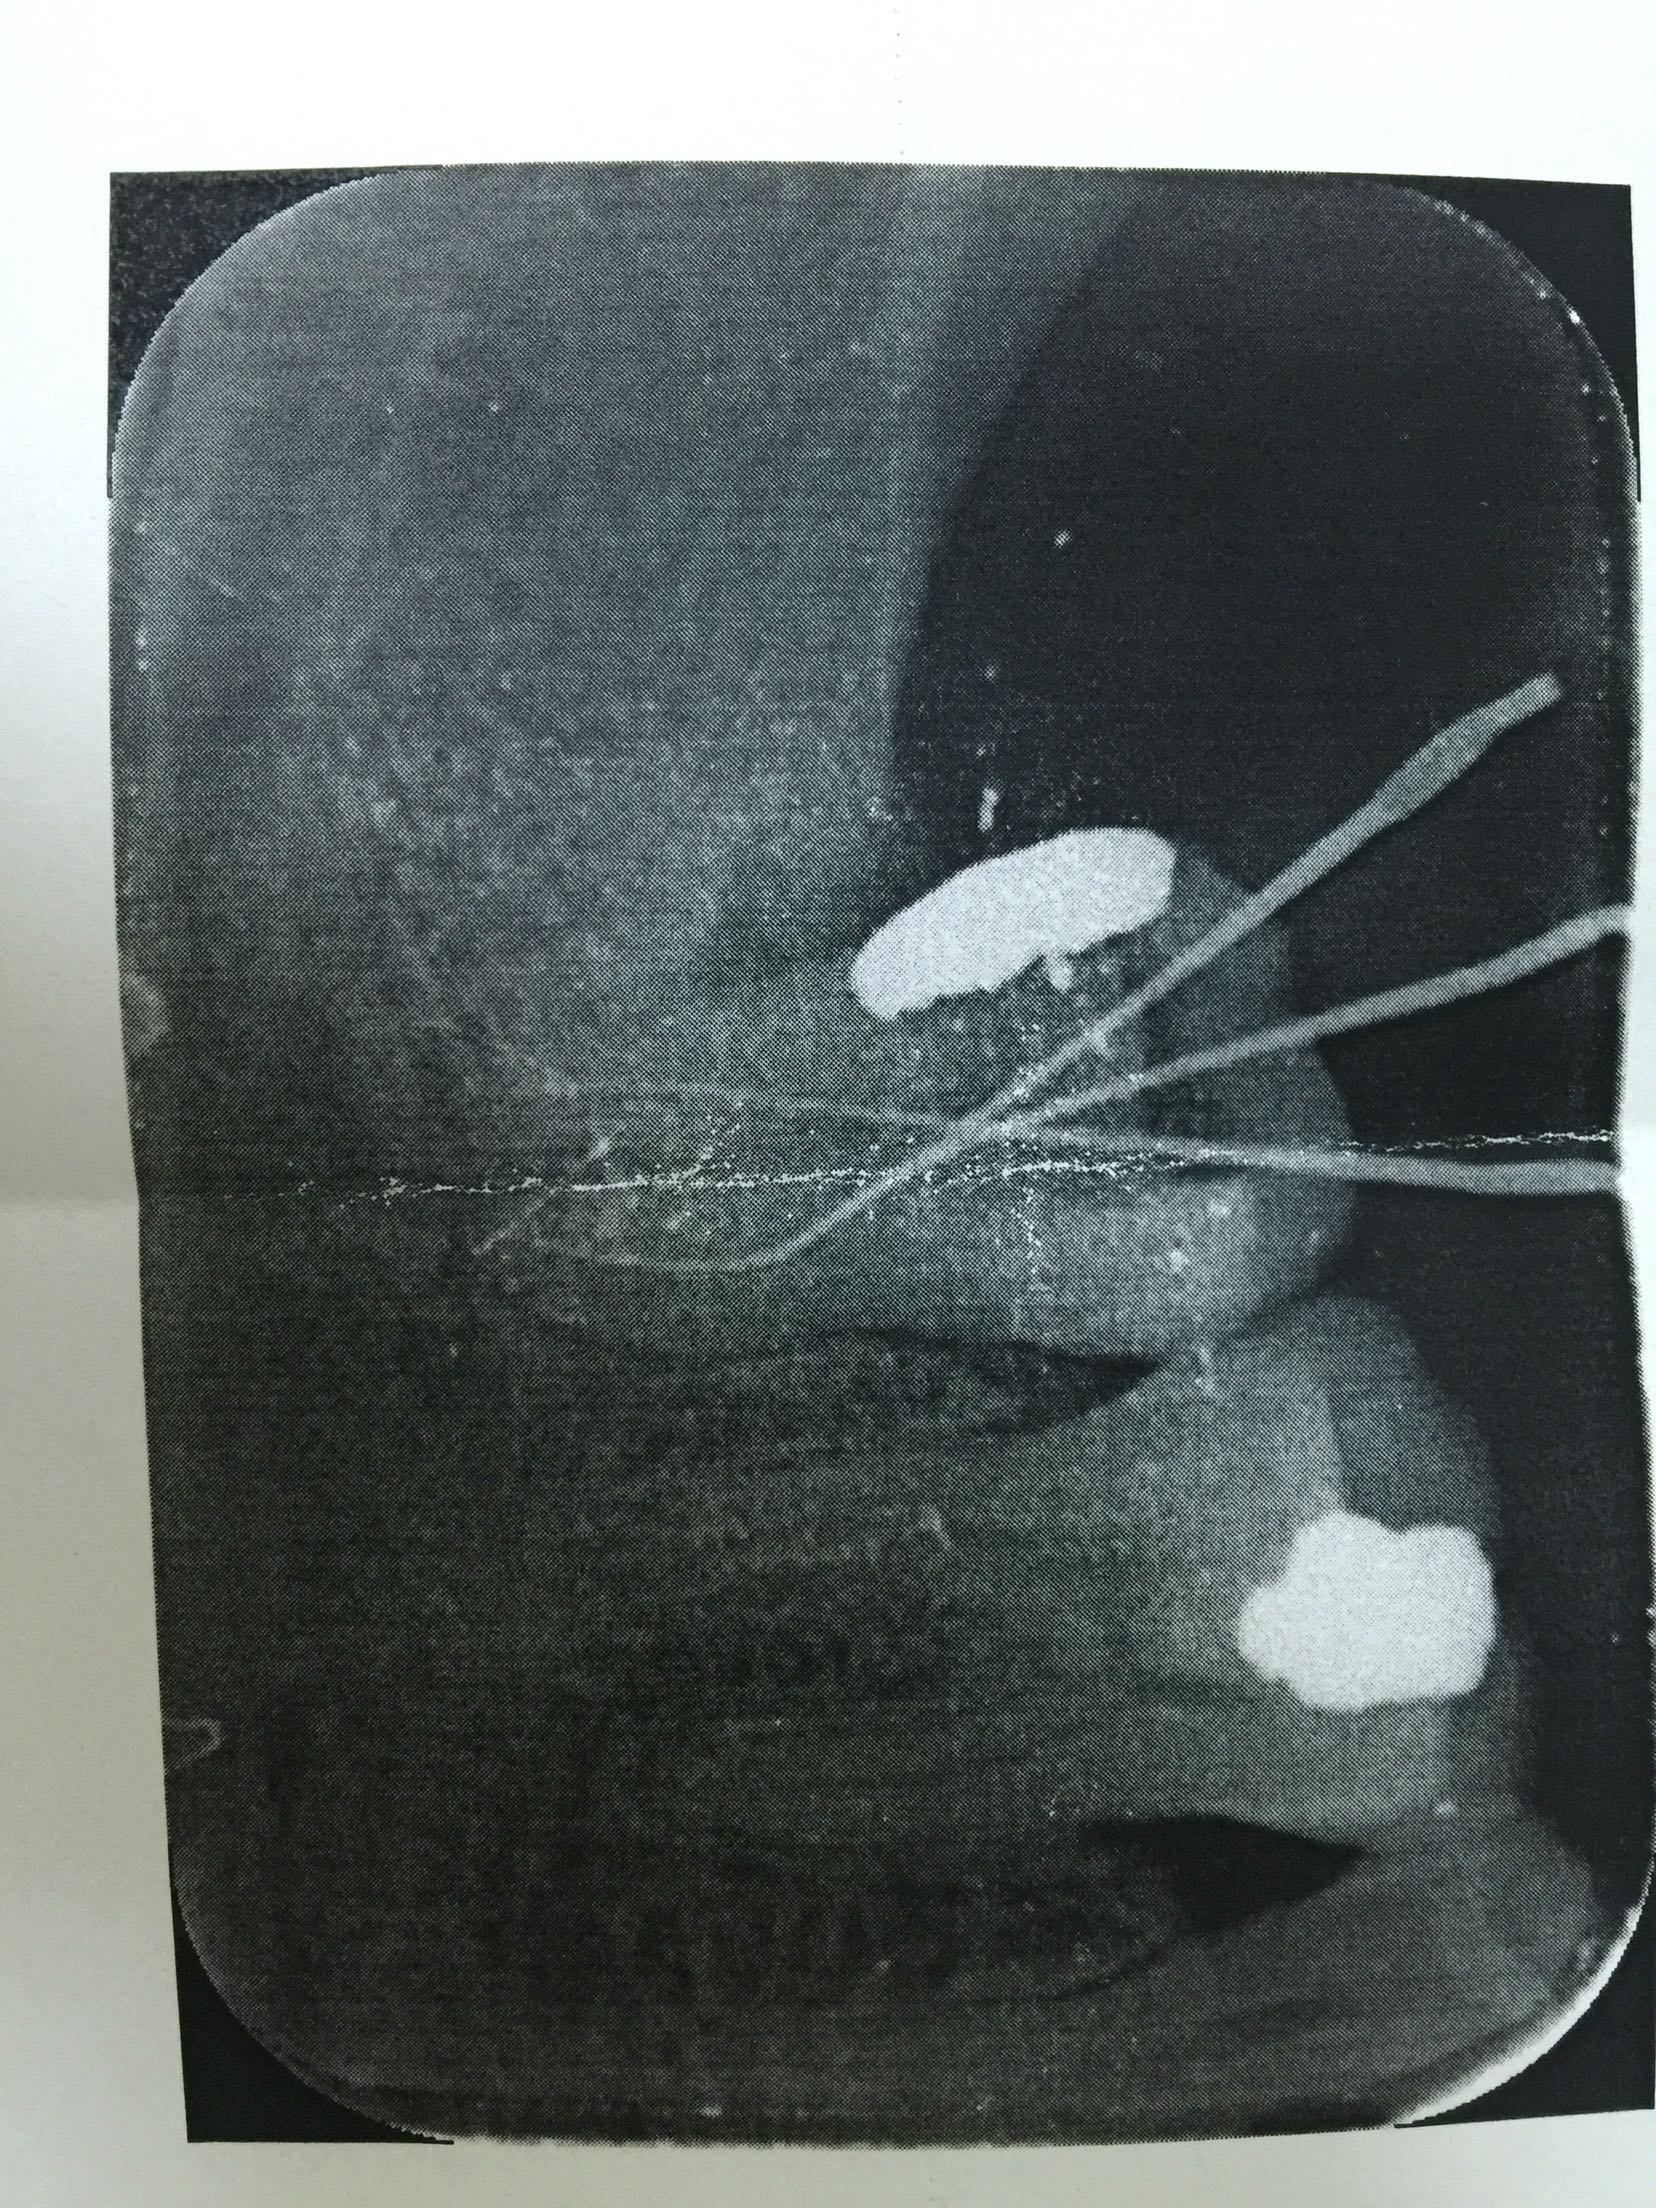

检查:47远中邻合面充填物存,叩诊(+-),松动不明显,牙龈无红肿,冷诊(++)。X线片示:47充填物近髓,根尖未见明显低密度影像。

诊断:47急性牙髓炎 治疗:47局麻下开髓揭顶全,慢失活,暂封,告医嘱,肿痛随诊。 47复诊,无不适。去暂封及失活剂,根管疏通,长度测量,waveone根管预备,冲洗,干燥,根管封药,告医嘱,肿痛随诊。 47复诊,无不适。47常规完成根充,建议冠修复。

此第二磨牙为双根管,也比较常见。下颌第二磨牙变异较大,多见的为C形根,三根管,双根管,单根管都有可能,临床中应注意辨别。